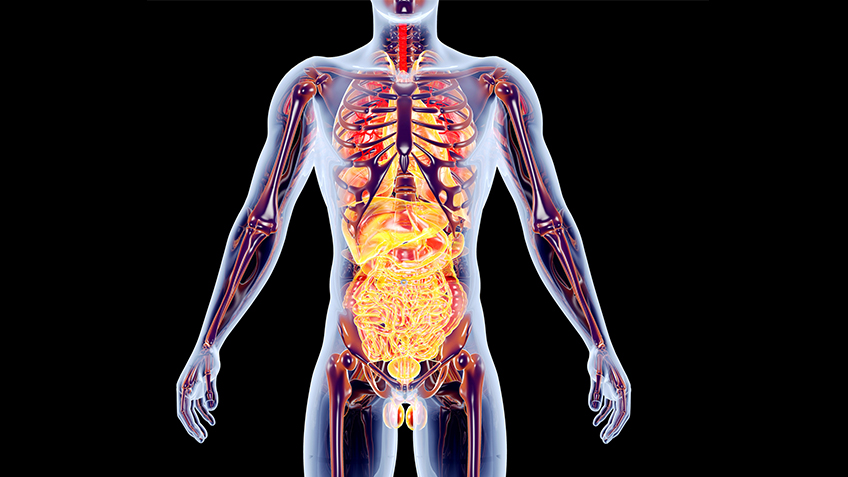

- Definition: Die Anatomie ist die Lehre vom Aufbau des menschlichen Körpers und seiner verschiedenen Organsysteme und Gewebearten. Dazu gehört auch die Embryologie, die sich mit der Entstehung der anatomischen Strukturen während der Embryonalentwicklung beschäftigt.

Wie ist der menschliche Körper aufgebaut? Diese Frage hat im Medizinstudium nicht ohne Grund einen hohen Stellenwert: Denn nur, wer versteht, wie ein gesunder Mensch “funktioniert”, kann Krankheiten erkennen und behandeln. Wie auch die Physiologie und die Biochemie gehört die Anatomie zum vorklinischen Teil des Medizinstudiums, in dem die Grundlagen für den späteren Arztberuf gelegt werden.

Ein Untergebiet der Anatomie ist die Embryologie, die sich mit der Entstehung und Entwicklung des menschlichen Körpers im Mutterleib beschäftigt. Außerdem gehört die Histologie zur Anatomie: Dieses Fachgebiet beschäftigt sich mit menschlichen Geweben und Zellen. Da diese feinen Strukturen mit bloßem Auge nicht erkennbar sind, spricht man auch von mikroskopischer Anatomie.